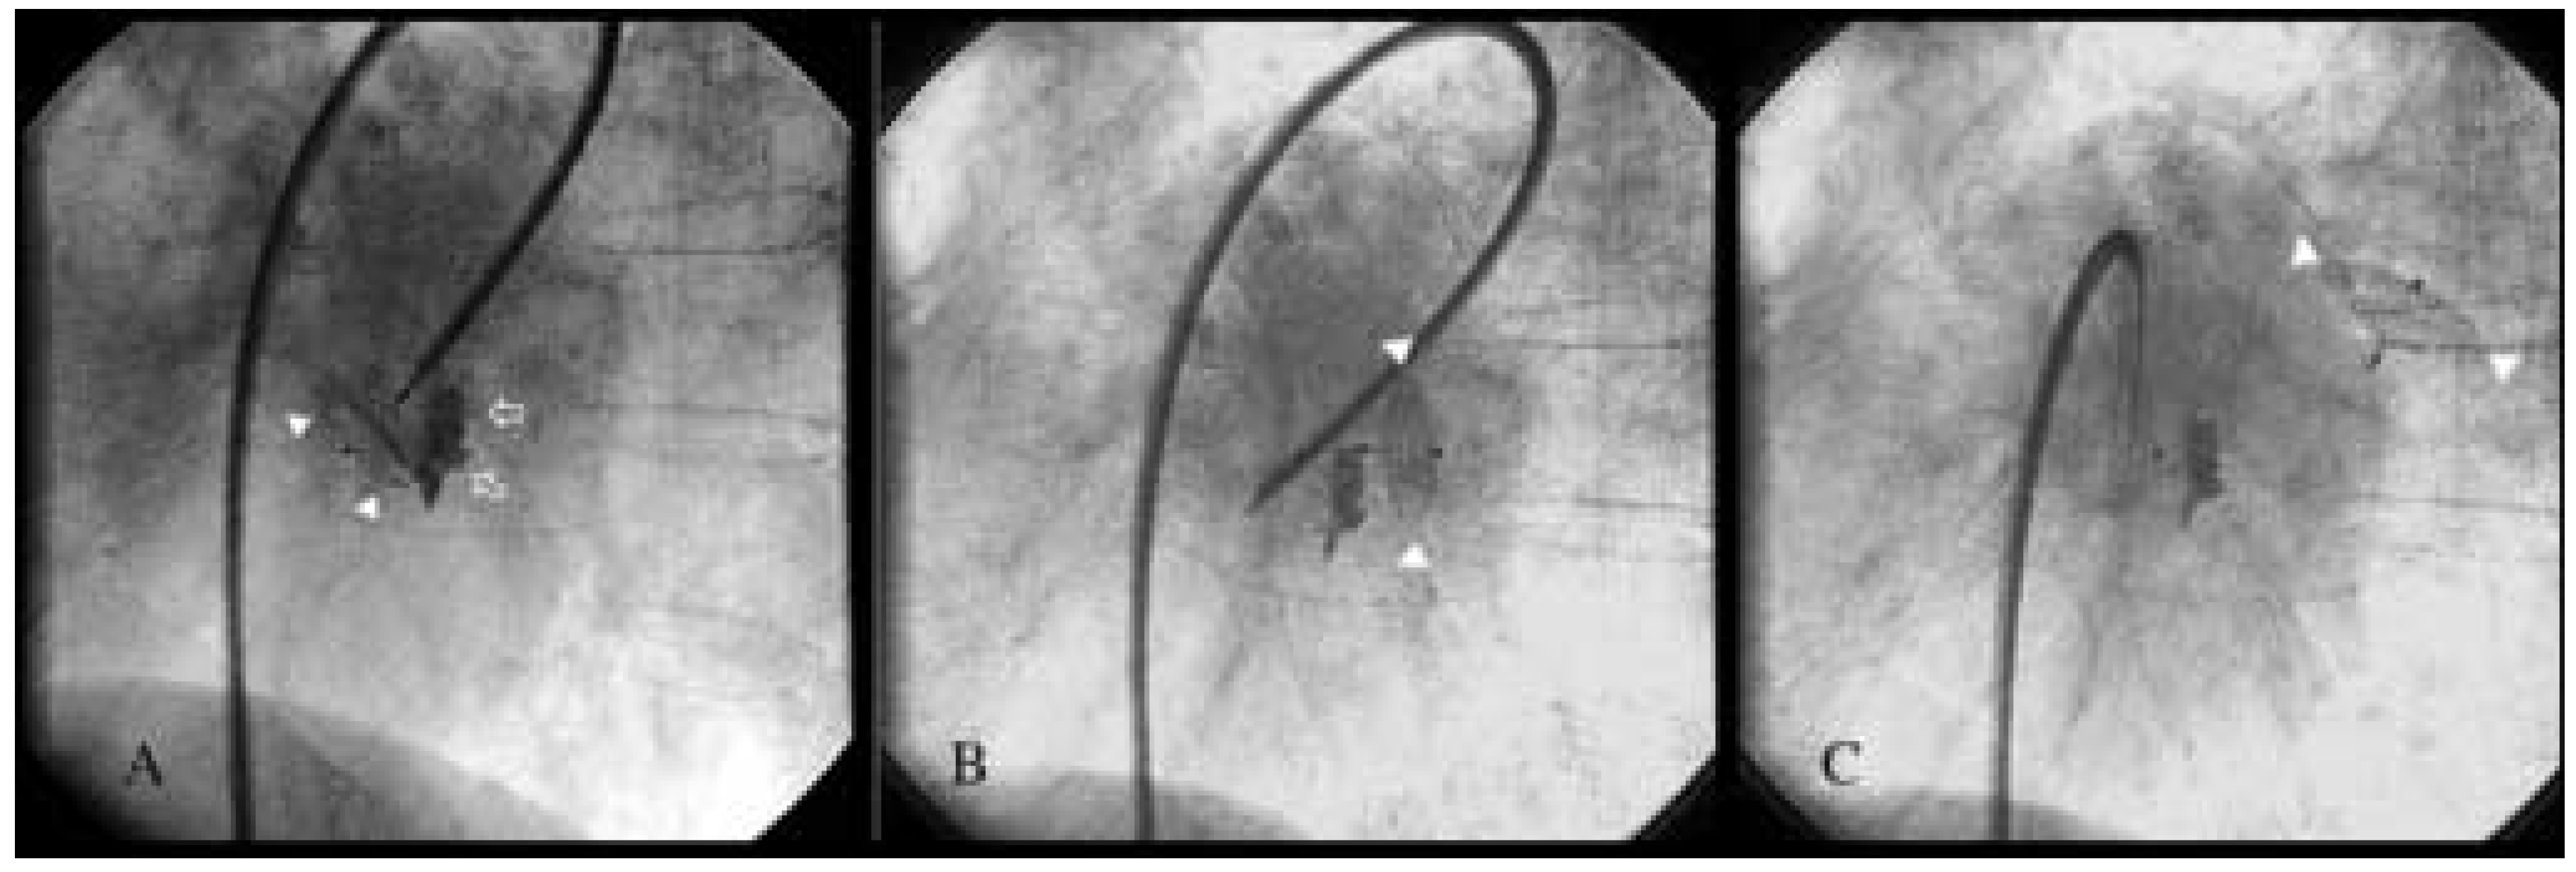

An 80-year-old woman with symptomatic rheumatic mitral valve disease and chronic atrial fibrillation was admitted for mitral valvuloplasty and interventional occlusion of the left atrial appendage. Mitral commissurotomy had been performed 30 years earlier. Because of unstable INR with warfarin therapy, she was at increased risk for bleeding and thromboembolism. The left atrium was grotesquely dilated (10.3 × 4.6 cm) and showed spontaneous echo contrast. Severe calcification of the mitral valve and mitral annulus resulted in significant stenosis (mitral valve area 1.0 cm2, mean pressure gradient 11 mm Hg) and mild mitral regurgitation. The coronary arteries were normal and mitral valvuloplasty was performed resulting in only moderate improvement with a valve area of 1.3 cm2. After fluoroscopic identification of the atypically located left atrial appendage by contrast medium injection, a 10 mm Amplatzer septal occluder was inserted (fig. 1A). However, after its detachment from the catheter, the device dislodged from the left atrial appendage and was found floating in the left atrium (fig. 1B, C). In light of the residual mitral stenosis with moderate regurgitation, no attempt was made to retrieve the dislodged device percutaneously. The patient was left with bed rest and heparin. The next day the device was still in the left atrium (fig. 2) and mitral valve replacement was performed. The occluder was removed from the left atrium and found clean from thrombosis (fig. 3). An atrial septal tear resulting from the transseptal puncture was repaired, and the left atrial appendage was obliterated. Postoperative recovery was uneventful.

Figure 3. Removed device showing some fibrinous coating but not clot.